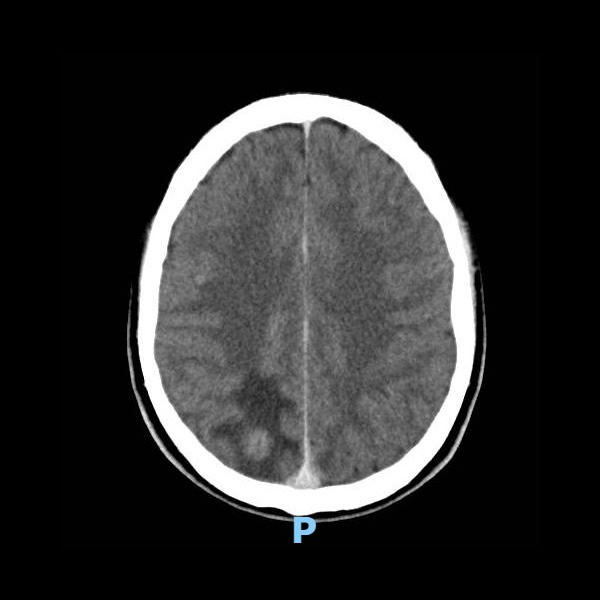

Junio 2022. Instituto Roentgen MASCULINO 19 AÑOS APP: NIEGA. ATX: NIEGA. AHF: NIEGA MH: NIEGA MC: CEFALEA, CONVULSIONES